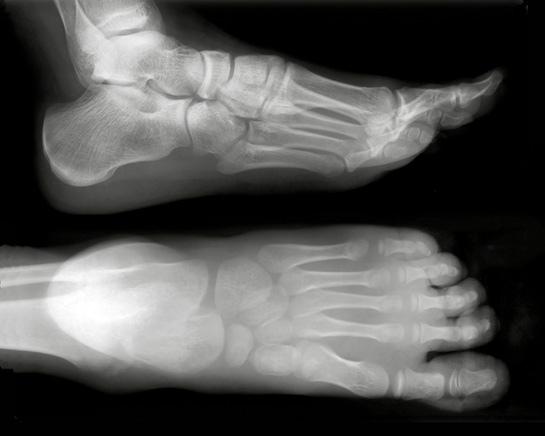

Ayak Bileği Çatlağı Nedir?

Ayak bileği çatlağı, ayak bileğindeki kemiklerin (genellikle tibia, fibula veya tarsal kemikler) bütünlüğünün bozulmasıyla oluşan bir yaralanmadır. Bu tür yaralanmalar, çeşitli derecelerde olabilir ve genellikle aşağıdaki belirtilerle kendini gösterir:

Tedavi Yöntemleri

Ayak bileği çatlaklarının tedavi süreci, yaralanmanın tipine ve ciddiyetine bağlı olarak değişir. Tedavi yöntemleri genel olarak şu şekildedir: